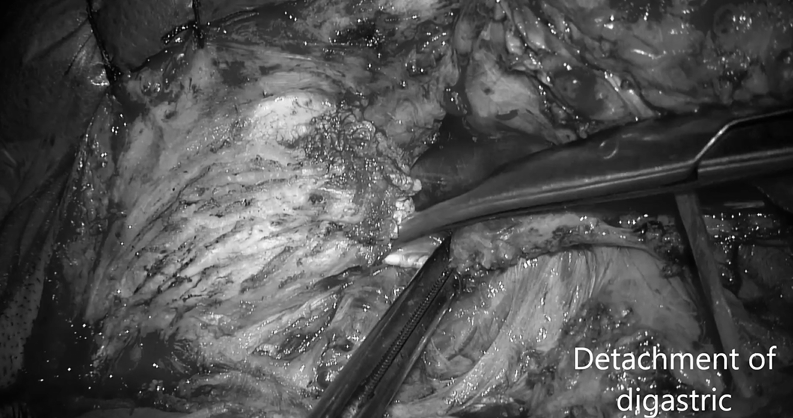

▼二腹肌分离